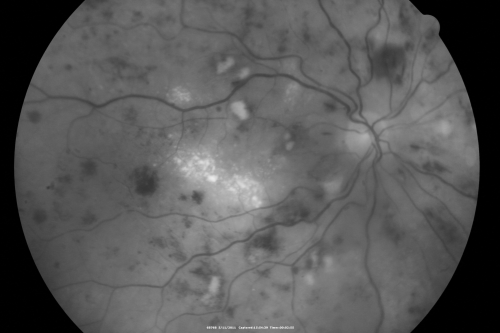

Malignany Hypertension - BP 250/130 - Vision 1/200 in each eye - Diabetic

68-year-old woman poor vision in both eyes for the last few years.  She is diabetic since 1989.  Her blood pressure has been very high.  She was in the hospital Friday.  Her blood pressure during that visit was 250/130 and her blood pressure in your office she reports was somewhere around the same.  I just checked her blood pressure at the beginning of my visit and it was 200/120 in her right arm sitting.  Her vision is poor enough that she can barely see to walk around.  She has also been feeling nauseous